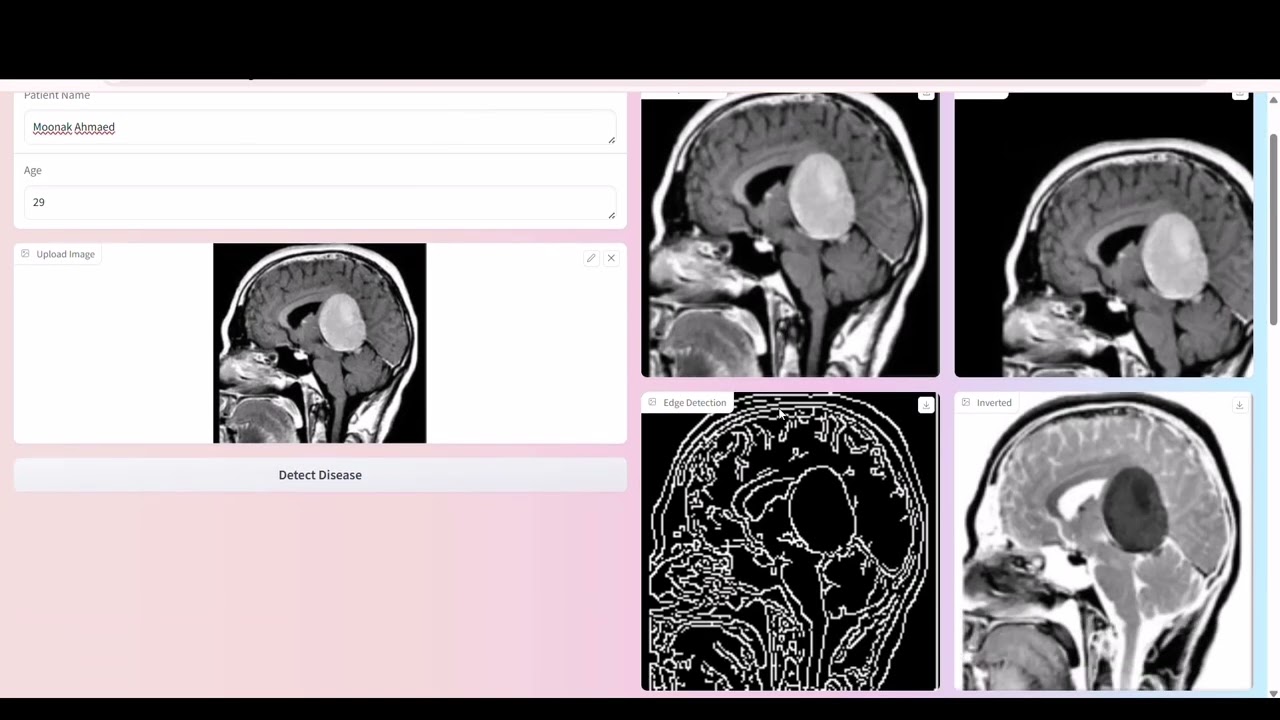

The NeuroVision system integrates brain imaging data into a unified smart platform, enabling healthcare professionals to visualize, and analyze brain MRI scans with precision. Powered by deep learning and intelligent automation, NeuroVision delivers real-time tumor detection, rapid diagnostic reporting, and accurate planning tools. By enhancing clinical decision-making and supporting early diagnosis, the system contributes to smarter healthcare solutions and aligns with national and global healthcare innovation goals.